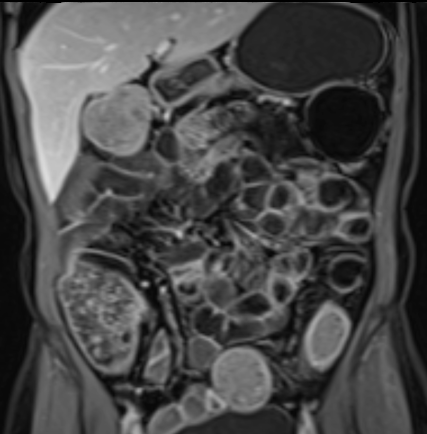

Phát hiện hẹp lòng ruột ở đại tràng sigma, không thể vượt qua được khi nội soi.

MR-enterography được thực hiện để đánh giá mức độ lan rộng của chỗ hẹp.

Ruột non bình thường, nhưng ghi nhận các đoạn hẹp ở đại tràng xuống và đại tràng ngang.

Cả hai đoạn hẹp đều có thành ruột dày đến 8 mm và ngấm thuốc rõ rệt theo kiểu niêm mạc ở đại tràng xuống và kiểu phân lớp ở đại tràng ngang.

Giãn ruột trước chỗ hẹp được ghi nhận ở cả hai đoạn.

Do các chỗ hẹp này không hiện diện khi nội soi đại tràng trước khi điều trị kháng TNF, nhiều khả năng chúng đã hình thành trong quá trình điều trị.

Do đó, quyết định phẫu thuật cắt đại tràng gần toàn bộ với miệng nối hồi-sigma đã được đưa ra.